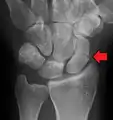

A subtle scaphoid fracture

A more obvious scaphoid fracture on a scaphoid view X ray

Radiolucency around a 12 days old scaphoid fracture that was initially barely visible.[10]